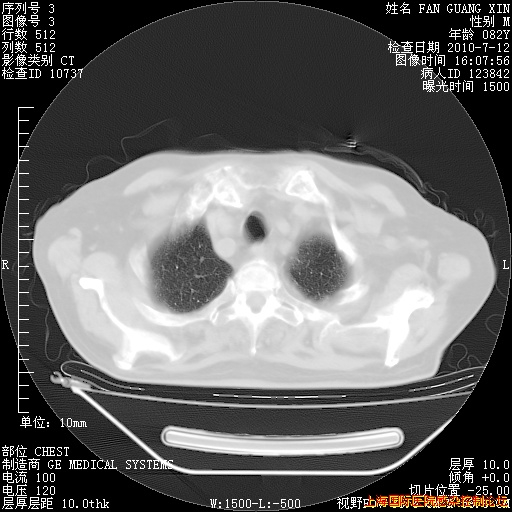

补发6月12日肺部CT肺窗

回复

今天复查CT

整整相隔30天的肺部CT好像有所好转啊。甲强龙减量第3天,需要观察体温。

海管,自昨日你和我通完话后,不知您岳父消化道症状有无缓解?体温怎样?阅读7.12日胸部ct,个人认为目前激素治疗是有效的,甲强龙减量是适宜的。因在抗痨治疗,需密切观察肝功、肾功能和血常规。不过,老年、长期住院和大量使用激素,很担心菌群失调发生